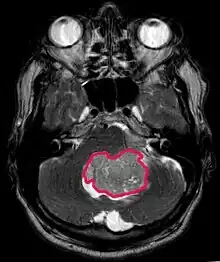

Medulloblastomes

Le médulloblastome est la tumeur cérébrale maligne la plus fréquente chez l'enfant. L'incidence la plus élevée survient chez les enfants âgés de 2 à 7 ans. Le plus grand risque de maladie demeure dans l'enfance, car le médulloblastome est très rare chez les personnes de plus de 21 ans.

Cette tumeur est typique de la fosse postérieure, où elle est localisée dans les deux hémisphères du cervelet ou dans le vermis cérébelleux. Parce qu'il est envahissant et à croissance rapide, il se propage généralement à d'autres parties du système nerveux central (SNC) via le LCR et peut infiltrer le plancher du quatrième ventricule voisin et les méninges. Plus rarement, des métastases supplémentaires du SNC peuvent survenir. Lorsque la tumeur maligne survient, les symptômes comprennent la perte d'équilibre, l'incoordination, la diplopie, la dysarthrie et l'atteinte du quatrième ventricule, ce qui entraîne souvent une hydrocéphalie obstructive, des maux de tête, des nausées et des vomissements et une démarche instable.

L'IRM montre généralement une lésion de contraste massive impliquant le cervelet. Comme mentionné ci-dessus, le médulloblastome a une forte propension à infiltrer localement les leptoméninges ainsi qu'à se propager à travers l'espace sous-arachnoïdien, impliquant les ventricules, la convexité cérébrale et les surfaces leptoméningées de la colonne vertébrale. Par conséquent, il est nécessaire de mettre en résonance tout l'axe crânio-spinal.

Le but de la chirurgie est d'enlever autant que possible la masse présentée par la lésion. En effet, les tumeurs résiduelles postopératoires entraînent un moins bon pronostic. La présence de cellules tumorales dans le liquide céphalo-rachidien ou la détection par résonance de métastases leptoméningées est également un signe avant-coureur d'un pronostic défavorable. La chirurgie seule n'est généralement pas curative. Dans certains cas, cependant, une irradiation thérapeutique de l'axe craniospinal, focalisée sur le site tumoral primaire, peut en résulter. L'ajout d'une chimiothérapie après la radiothérapie augmente le taux de guérison. Des médicaments à base de platine (cisplatine ou carboplatine), de l'étoposide et un agent alkylant (cyclophosphamide ou lomustine) sont utilisés avec la vincristine. Avec un traitement approprié, les cas de longue survie de plus de 3 ans chez les patients atteints de médulloblastome varient de 60 à 60 ans et 80 Pour cent.